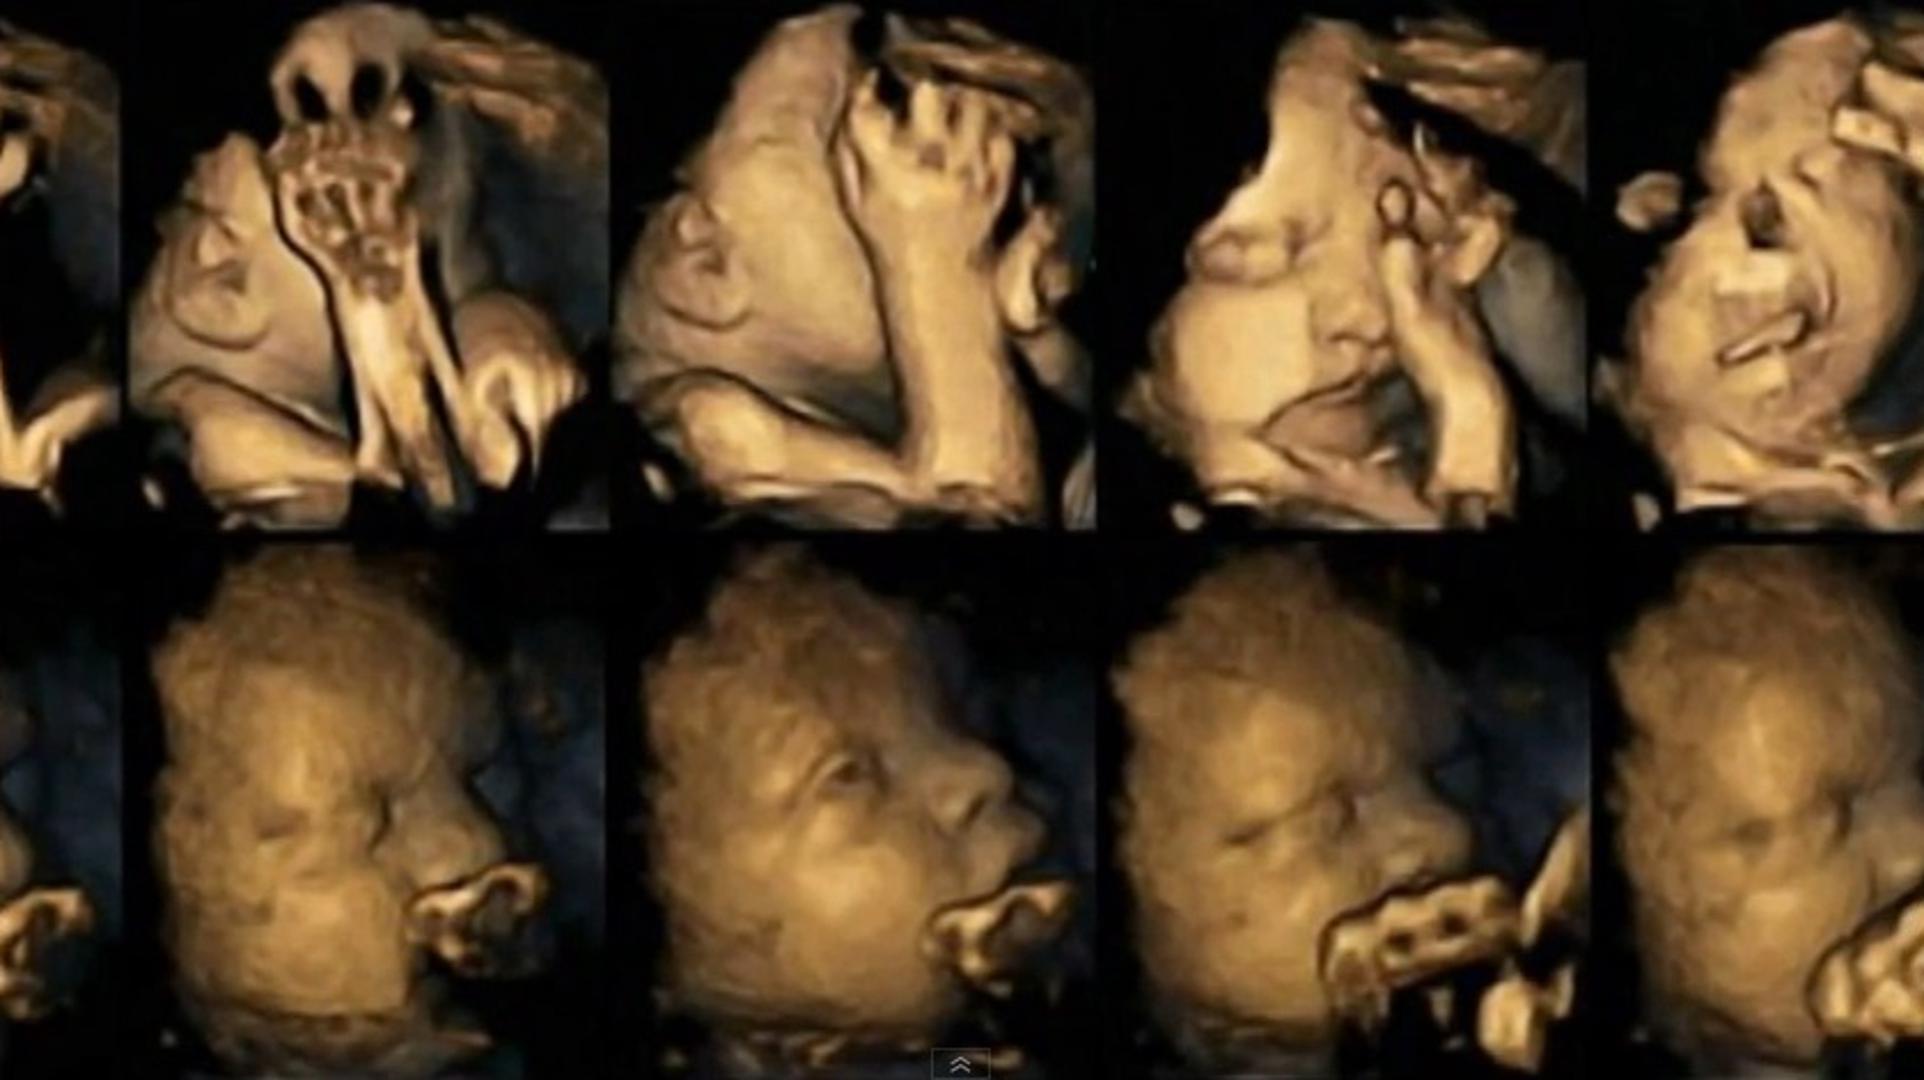

Ove 4D snimke otkrivaju kako pušenje utječe na bebe

Znanstvenici sa Sveučilišta Durham proučavali su razlike između 20 majki koje ne puše i onih koje puše, a razvoj bebe su pratili 4D ultrazvukom u 24., 28., 32. i 36. tjednu trudnoće.

Otkriveno je da se bebe pušača češće dodiruju po licu i ustima u odnosu na bebe nepušača jer s vremenom dobivaju veću kontrolu nad pokretima, odnosno brže se razvijaju.

Otkriveno je da pušenje usporava razvoj živčanog sustava kod nerođenog djeteta te je njihova kontrola pokreta smanjena, piše Daily Mail.

- Potrebna su daljnja istraživanja kako bi se utvrdile i veza stresa i pušenja. Ipak, nadamo se da bi već ovo istraživanje i snimke koje imamo mogle potaknuti trudnice da se odreknu cigarete - rekla je voditeljica istraživanja dr. Nadja Reissland.

Tehnologija nam omogućuje da vidimo stvari koje su prethodno bile skrivene, pa tako i utjecaj cigarete na nerođene bebe- dodao je jedan od voditelja istraživanja profesor Brian Francis.